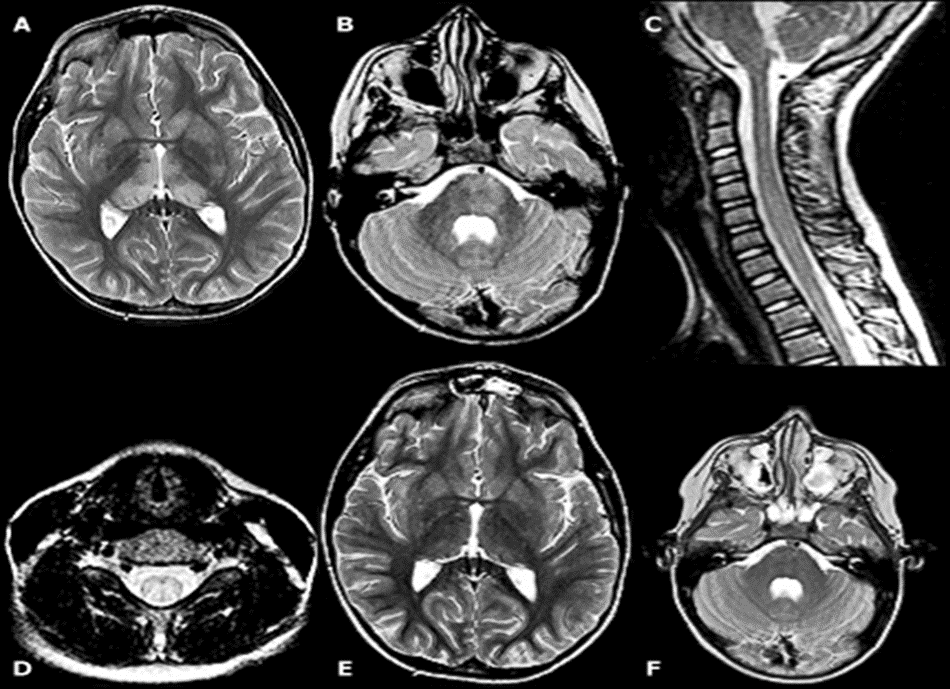

–მწვავე დისემინირებული ენცეფალომიელიტი – თეთრი ნივთიერების ღრმა და სუბკორტიკალური დაზიანებები, როგორც წესი, მრავლობითი და ორმხრივია, მაგრამ შეიძლება ასიმეტრიული იყოს (სურათი 2). ხშირია ტვინის ღეროს და ზურგის ტვინის ანომალიები. ნაცრისფერი ნივთიერების დაზიანებები შეიძლება შეინიშნოს თალამუსსა და ბაზალურ განგლიებში.

სურათი 2.

მწვავე დისემინირებული ენცეფალომიელიტის მქონე 7 წლის ბიჭის ტვინისა და ხერხემლის მაგნიტურ-რეზონანსული ტომოგრაფია.

(A) ტვინის აქსიალური T2-შეწონილი მაგნიტურ–რეზონანსული ტომოგრაფია აჩვენებს შედარებით სიმეტრიულ მაღალ სიგნალის ინტენსივობას ღრმა ნაცრისფერ ნივთიერებაში, მათ შორის ორმხრივ თალამუსში.

(B) ასევე მაღალია T2 სიგნალი ხიდის მარცხენა ასპექტში.

(C) კისრის ხერხემლის საგიტალური T2-შეწონილი მაგნიტურ–რეზონანსული ტომოგრაფია აჩვენებს გაფართოებას/შეშუპებას და მაღალ სიგნალის ინტენსივობას ზურგის ტვინში.

(D) შესაბამისი აქსიალური T2-შეწონილი მაგნიტურ–რეზონანსული ტომოგრაფია აჩვენებს, რომ მაღალი სიგნალი ძირითადად უკანაა.

(E და F) ერთი თვის შემდეგ, T2-შეწონილი ღერძული გამოსახულებები აჩვენებს ღრმა ნაცრისფერ ნივთიერებაში (E) და ხიდის ტვინში (F) არსებული მონაცემების გარჩევადობას.